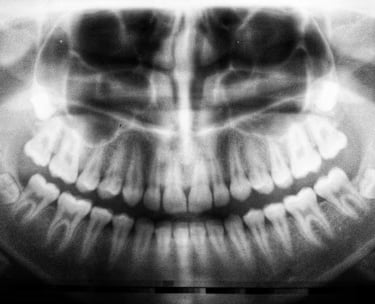

Comprehensive General Dentistry Services at Clinique Dentaire Pincourt

At Clinique Dentaire Pincourt, we take pride in offering top-notch general dentistry services to our community. Our commitment is to ensure that every patient enjoys a healthy, radiant smile through our comprehensive dental care. Whether you need routine check-ups or specialized treatments, our clinic is your trusted destination for general dentistry in Pincourt.